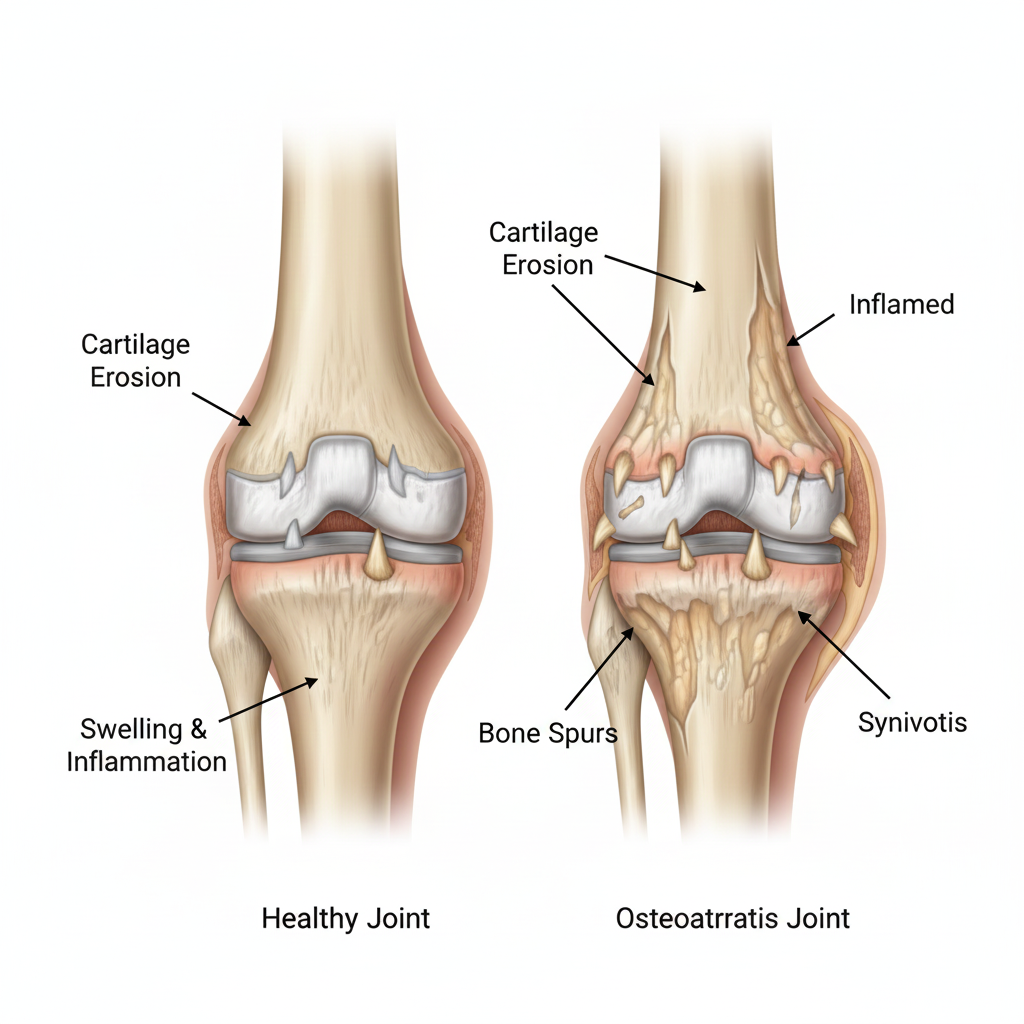

You may call it age-related wear and tear of the joint. The basic problem in Osteoarthritis is damage to the protective cartilage that covers the bone ends. The soft bone, cartilage gradually deteriorate over time and start causing pain and stiffness of the affected joint. Although osteoarthritis can affect any joint, it most frequently affects the weight-bearing joints such as knees, hips, and spine as well as can affect small joints of the hands

Swelling of the affected area